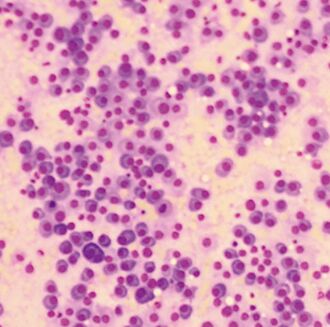

健保署引進美國CAR-T 有望用於多發性骨髓瘤

CAR-T細胞免疫治療第2項產品有望輸台 健保署拚落地